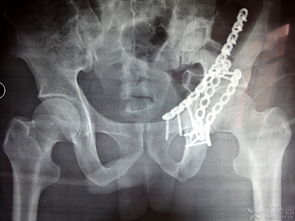

髖臼骨折,恥骨骨折,經(jīng)檢查無需住院,2回答者:lianghuanjie